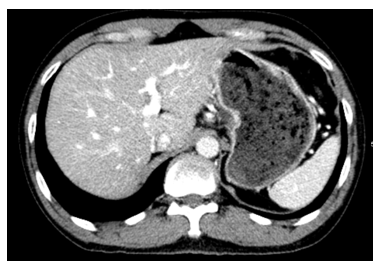

- Chụp cắt lớp vi tính ổ bụng: chưa phát hiện tổn thương thứ phát

Hình 2: Hình ảnh chụp cắt lớp vi tính ổ bụng: chưa phát hiện bất thường